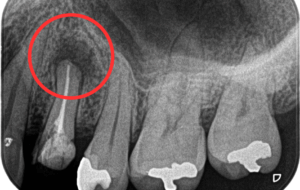

レントゲン検査で分かること

根尖性歯周炎は、見た目だけで診断することはできません。

そのため、レントゲン検査が非常に重要になります。

レントゲン写真では、歯の根の先に黒い影が見えることがあります。これは、炎症によって骨が吸収されている状態を示しています。

当院では、必要に応じて歯科用CTを使用し、根の形や炎症の広がりを立体的に確認します。これにより、より正確な診断と治療方針の判断が可能になります。